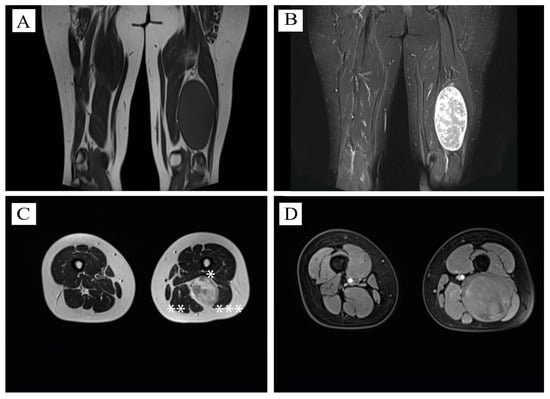

2.2. MRI Aspect

| Present case | Hypointense T1WI, Hyperintense T2WI, solid mass | 14 × 7 cm | |